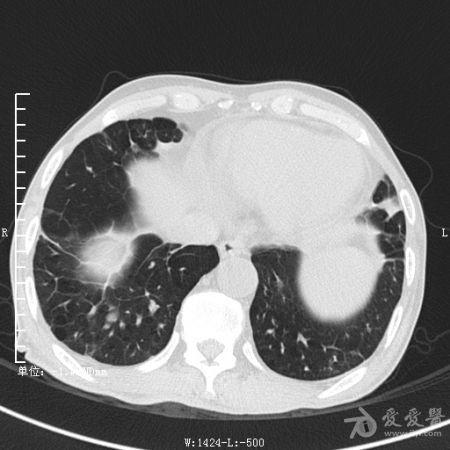

典型支气管扩张及肺水肿CT片

典型支气管扩张肺水肿